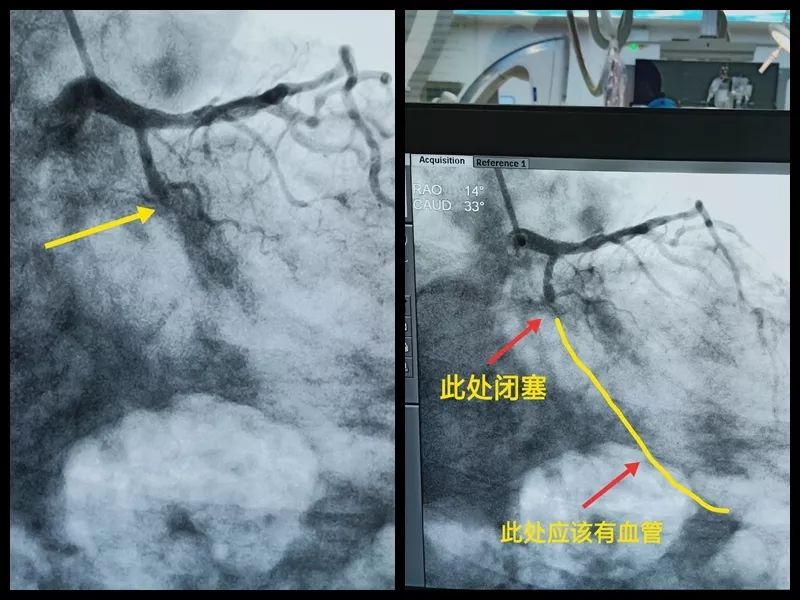

今天小编就在北京胸科医院心脏中心手术室遇到一个,中年男性,近期觉得憋喘,难受。上台造影发现,回旋支100%闭塞,也就是我们说的完全堵死,不过血了。

从造影可以看出来,患者的回旋支在箭头这个位置向下,看不见了。

这就是冠状动脉慢性完全闭塞(chronic total occlusion, CTO)。它是指冠状动脉100%闭塞且闭塞超过3个月的病变,具有再发病率高和再闭塞率高的发病特征,治疗难度大, 介入治疗平均成功率大约为40%~60%,是冠脉介入治疗目前面临的最大难题,被称为“未被攻克的最后的堡垒”。